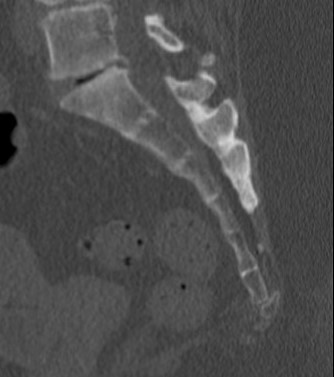

Xray

Dynamic radiographs

- standing and sitting radiographs

- looking for hypermobility

- > 25o

Spicule on coccyx

- may be seen in immobile coccygodynia

Posterior displaced coccyx fracture